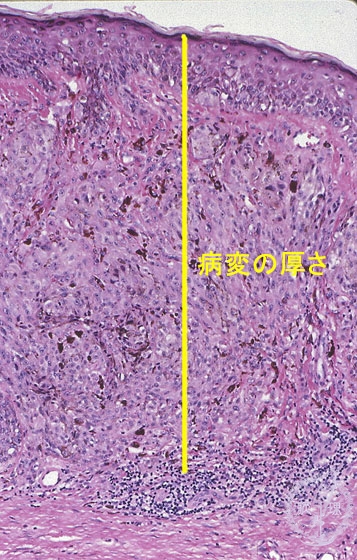

- ★(10)Malignant melanoma

Microscopic findings: Primary lesions show intraepidermal spread. Tumor cells usually have melanin pigments which is reflected in a macroscopic black color. Characteristic of these lesions and different from benign melanocytic nevus melanin pigmentation is also seen in the deep (distal to skin surface) area.